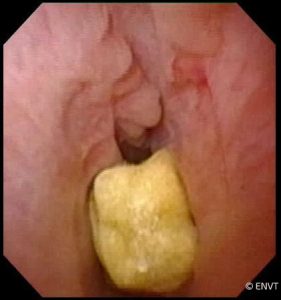

Calcul au niveau de l’urètre

- la lithotripsie (fragmentation au laser des calculs urétraux et vésicaux),